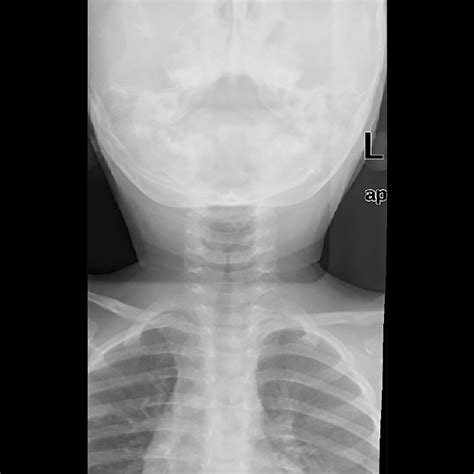

The Steeple Sign Croup is a specific finding observed on a frontal chest or neck X-ray. When a child with suspected croup undergoes imaging to rule out other, more serious causes of airway obstruction, radiologists look at the column of air within the trachea.

Normally, the trachea appears relatively straight on an X-ray. However, in cases of significant subglottic inflammation (swelling just below the vocal cords), the air column becomes narrowed. On the X-ray, this narrowing creates a shape that resembles the sharp, pointed roof of a church steeple, hence the name Steeple Sign.

It is important to note that this sign is radiographic—it is seen on imaging, not by looking at the child. Furthermore, not every child with croup will demonstrate the steeple sign on an X-ray, and not every child with croup requires an X-ray to be diagnosed.